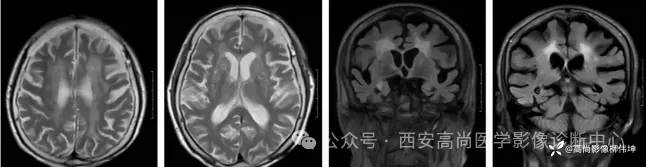

MR影像图

横轴位 T2WI 横轴位 FLAIR 横轴位 T1WI

矢状位 T2WI 冠状位 FLAIR

MR平扫+DWI+MRS:双侧额叶、半卵圆中心、侧脑室旁、胼胝体白质区见片状稍长T1稍长T2信号,FLAIR像显示高信号,边缘模糊,DWI像上病灶边缘见条片状高信号,ADC图上呈稍低信号,MRS示:上述病灶CHO波未见增高,NAA波未见减低,CHO/NAA为0.58。

诊断:双侧额叶、半卵圆中心、侧脑室旁、胼胝体区对称性脑白质脱髓鞘,考虑神经元核内包涵体病可能。

影像表现:皮髓质交界区广泛DWI鸡冠花样、曲线样高信号、胼胝体DWI高信号、对称性脑白质病变、皮层肿胀、广泛性脑萎缩。